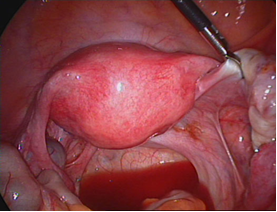

LNMTC phúc mạc mức độ tối thiểu (độ I) |

LNMTC phúc mạc mức độ nhẹ (độ II) |

LNMTC phúc mạc mức độ vừa (độ III) |

LNMTC phúc mạc mức độ nặng (độ IV) |